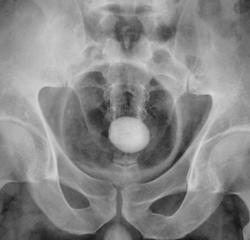

Мы, с учетом всего, что насторожило решили начать исследование с пневмоцистографии.

Фрагменты с увеличением.

Камень камнем, как объяснить этот мышинный хвостик внизу, а не обрубленная тень мочеточника? Приобретенный стеноз? выраженная стриктура? врожденная аномалия-мегауретер? или все таки стелещееся по стенке и устье образование? Хотя на пневмограммах стенка вполне приличная.